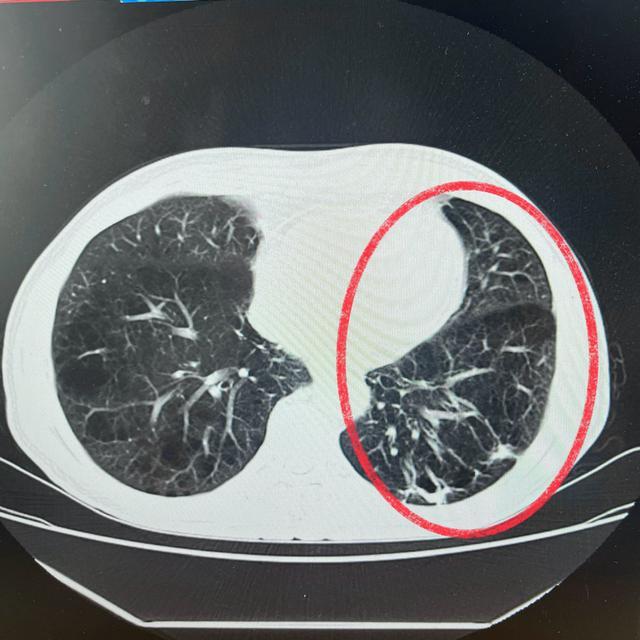

(一个月后复查)

一个月后,唐爷爷再次来到石门县中医医院进行复查。检查结果显示,他的身体状况较出院前有了显著的改善。面对这份来之不易的好转,唐爷爷的脸上洋溢着幸福的笑容,他笑眯眯地向肺病科医护人员竖起了大拇指,表达着对他们工作的肯定与感激。